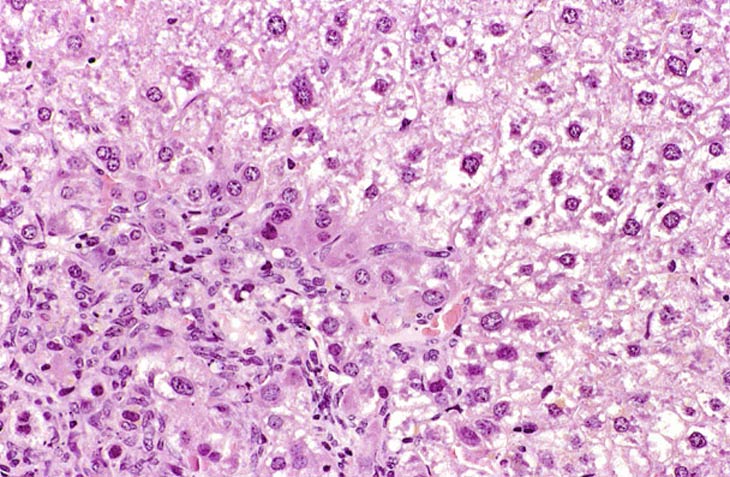

This change was originally diagnosed as endothelial cell proliferation. Based on the H&E stained sections, it is not possible to definitively identify the proliferating sinusoidal lining cells as endothelial cells but some have cytomorphological features consistent with endothelial cells. Low and high magnifications of endothelial cell hyperplasia.